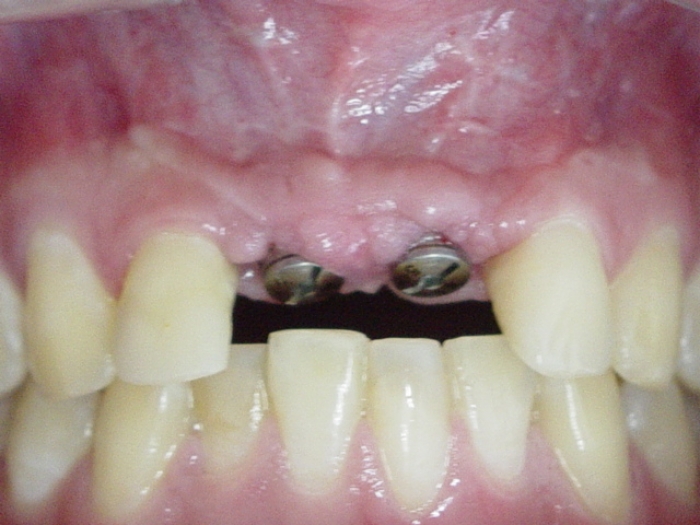

Dois implantes instalados, com cicatrizadores